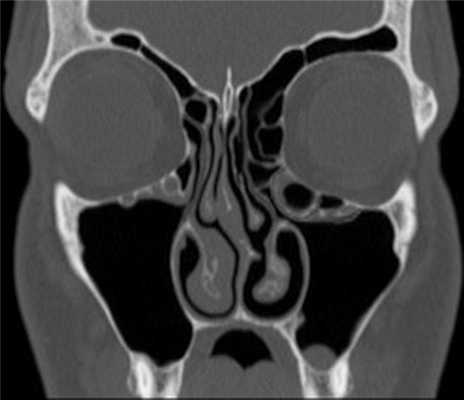

(Слева) На аксиальной КЛКТ справа и слева визуализируются добавочные устья ниже уровня соответствующих крючковидных отростков. Основные устья находятся на другом уровне и не видны на этом срезе.

(Справа) На корональной КЛКТ у этого же пациента визуализируются дополнительные устья справа и слева. Основные устья на этом срезе не видны. Обратите внимание на субтотальное снижение пневматизаци левой верхнечелюстной пазухи.